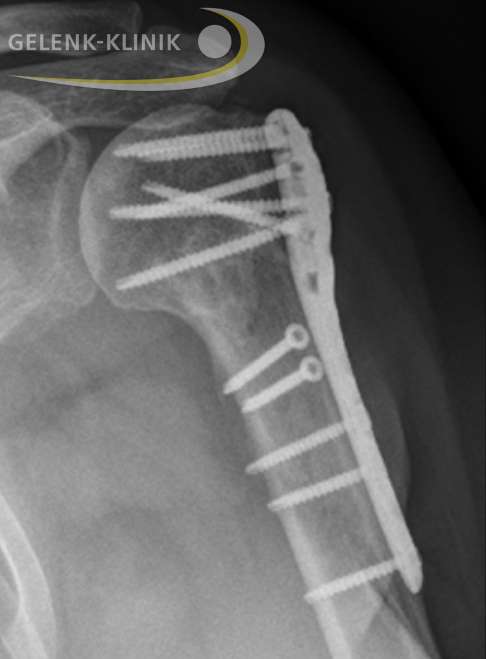

Die Osteosynthese

Mittels Osteosynthese werden die einzelnen Knochenteile in die korrekte Stellung und Achse zum restlichen Oberarm gebracht. Der Operateur fixiert die Knochenfragmente in dieser Position mittels Schrauben und Platten. Der Oberarmkopf des Patienten kann somit erhalten werden.